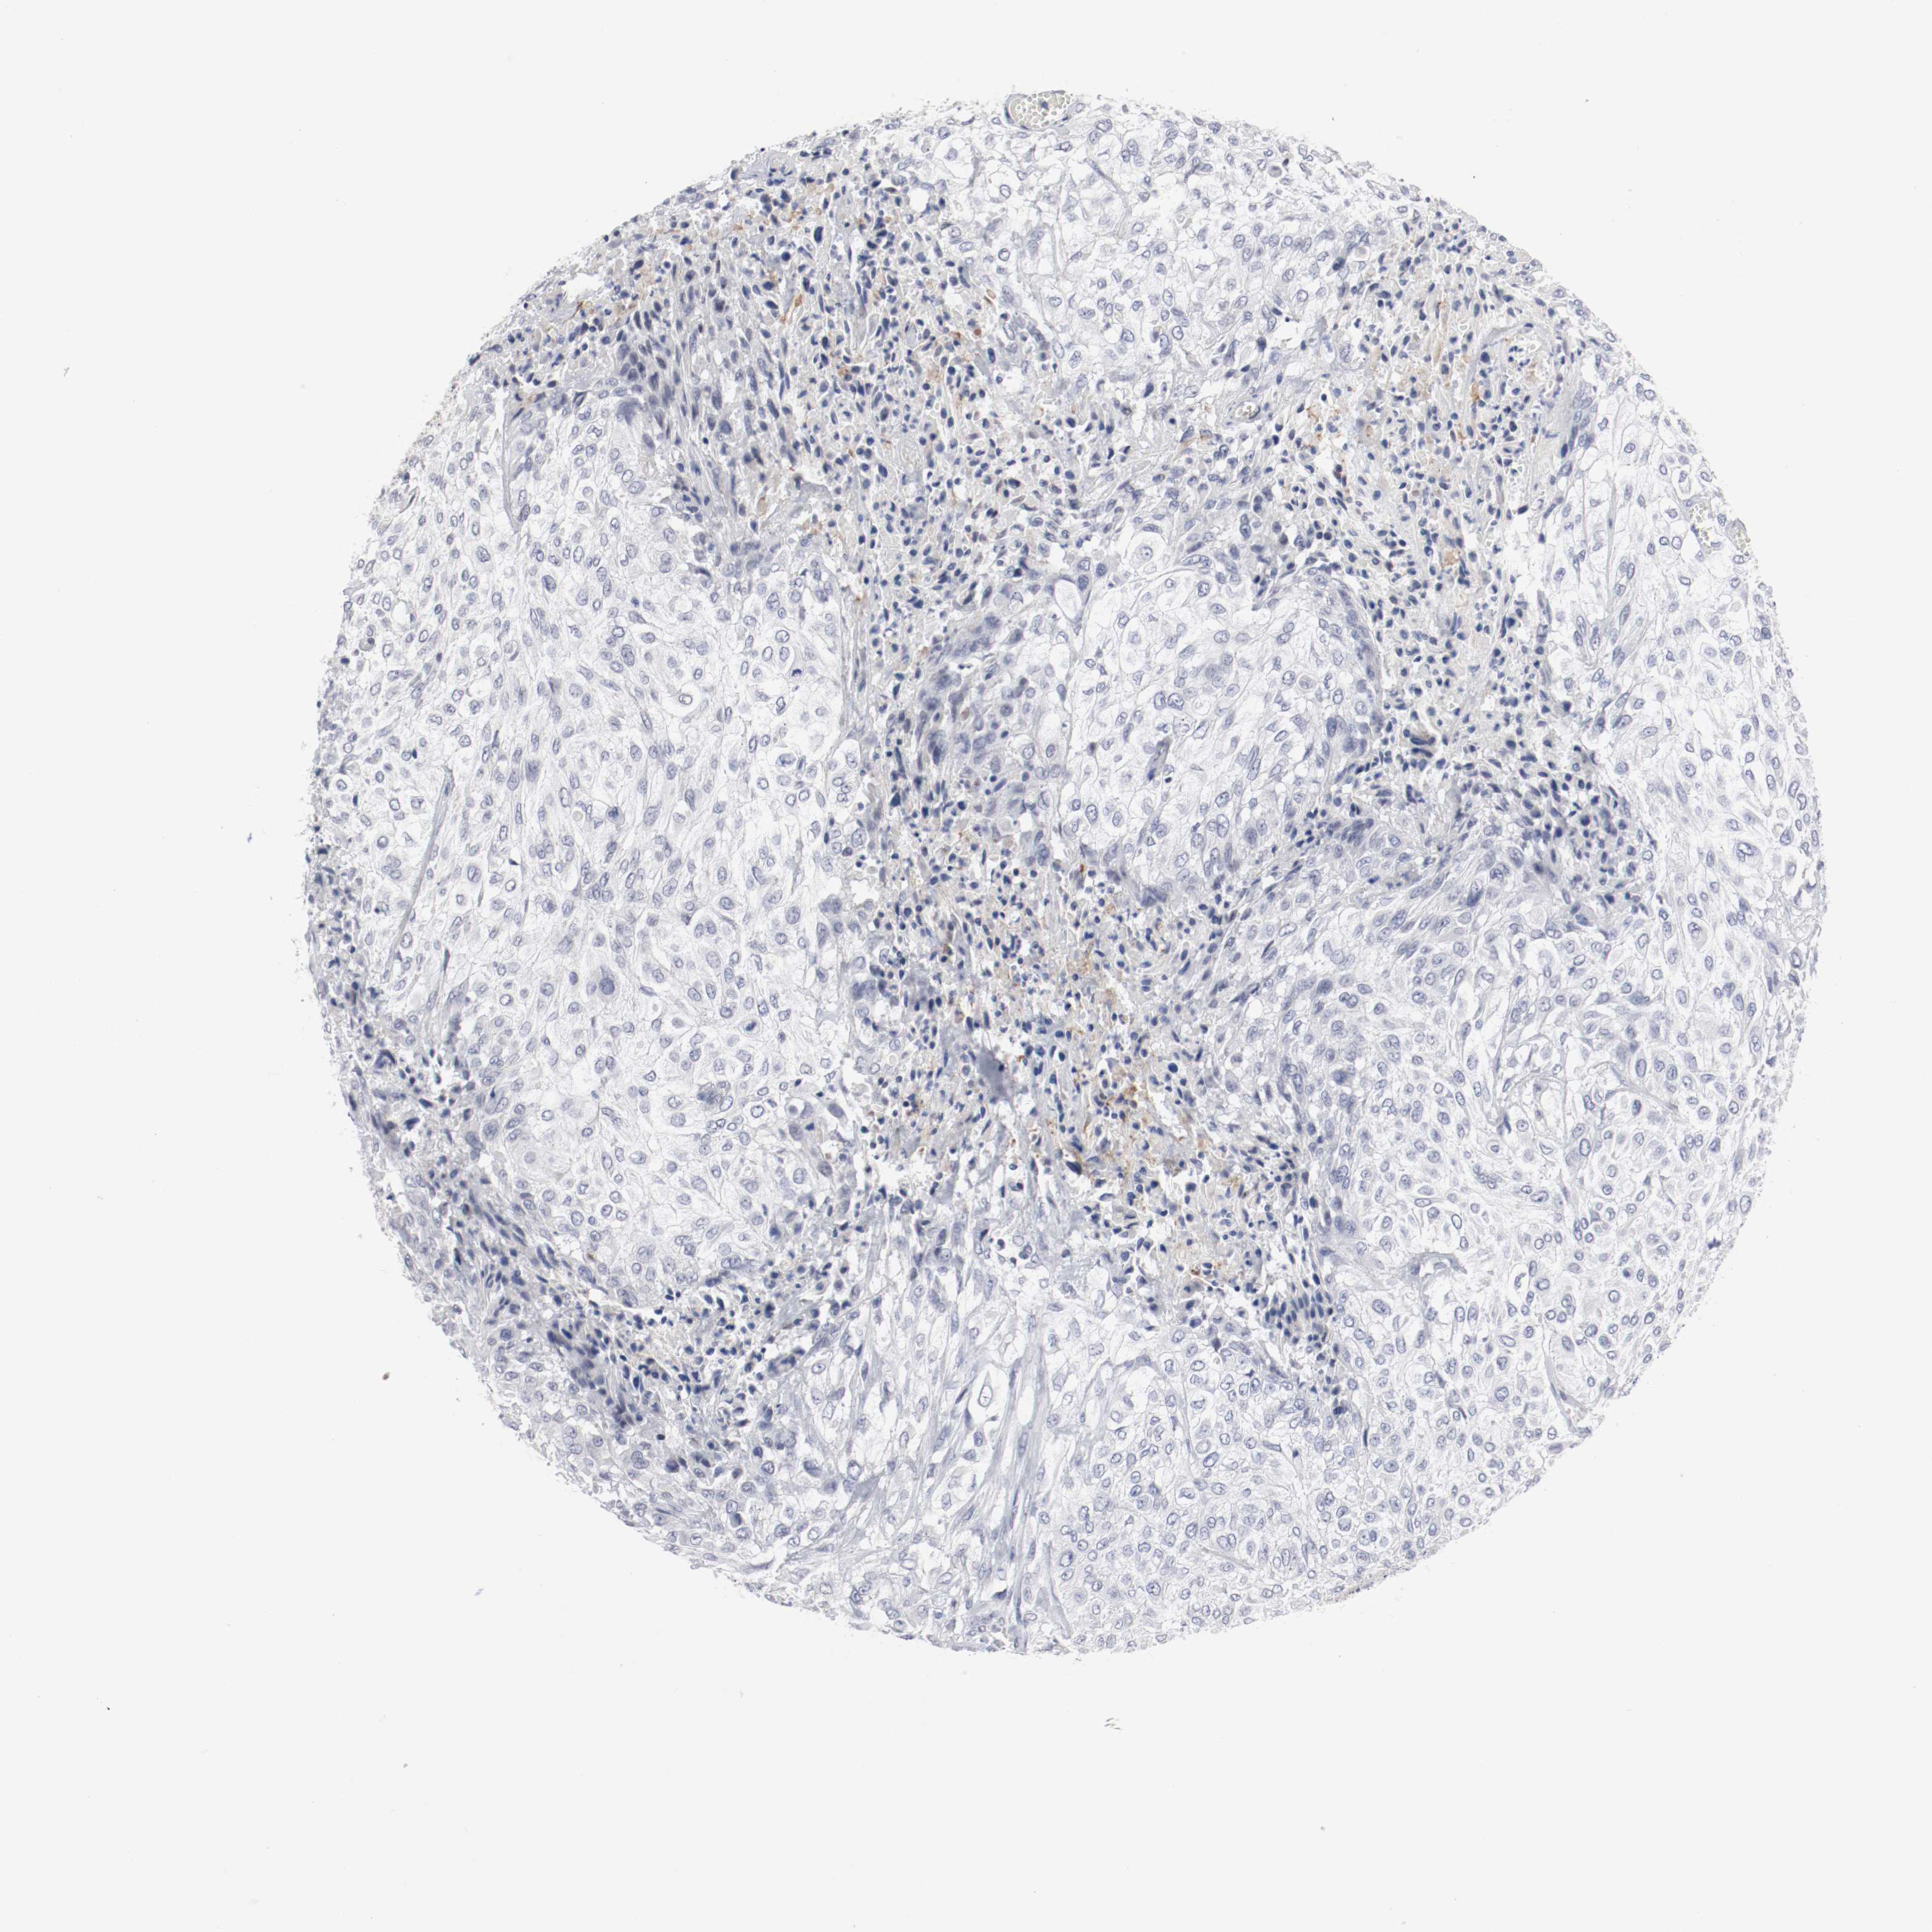

UROTHELIAL CANCER - Protein expressioni

A mouse-over function shows sample information and annotation data. Click on an image to view it in a full screen mode. Samples can be filtered based on level of antibody staining by selecting one or several of the following categories: high, medium, low and not detected. The assay and annotation is described here.

Note that samples used for immunohistochemistry by the Human Protein Atlas do not correspond to samples in the TCGA dataset.

Antibody stainingi

Antibody staining in the annotated cell types in the current human tissue is reported as not detected, low, medium, or high, based on conventional immunohistochemistry profiling in selected tissues. This score is based on the combination of the staining intensity and fraction of stained cells.

Each image is clickable and will lead to virtual microscopy that enables deeper exploration of all samples and also displays staining intensity scores, fraction scores and subcellular localization as well as patient and tissue information for each sample.

Antibody HPA004471

Antibody CAB003288

Antibody CAB068253

Antibody CAB072867

Staining

High

Medium

Low

Not detected

Intensity

Strong

Moderate

Weak

Negative

Quantity

>75%

75%-25%

<25%

None

Location

Nuclear

Cytoplasmic/membranous

Cytoplasmic/membranous,nuclear

Urothelial carcinoma, High grade

Urothelial carcinoma, Low grade

Adenocarcinoma, NOS

Urothelial carcinoma, NOS